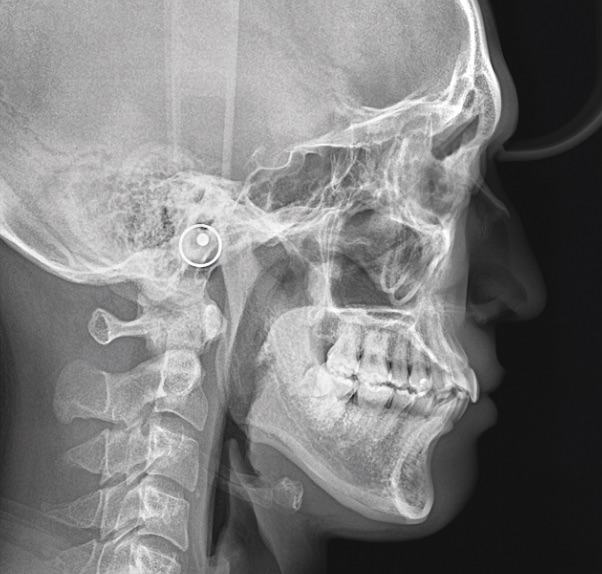

セファロ側方撮影